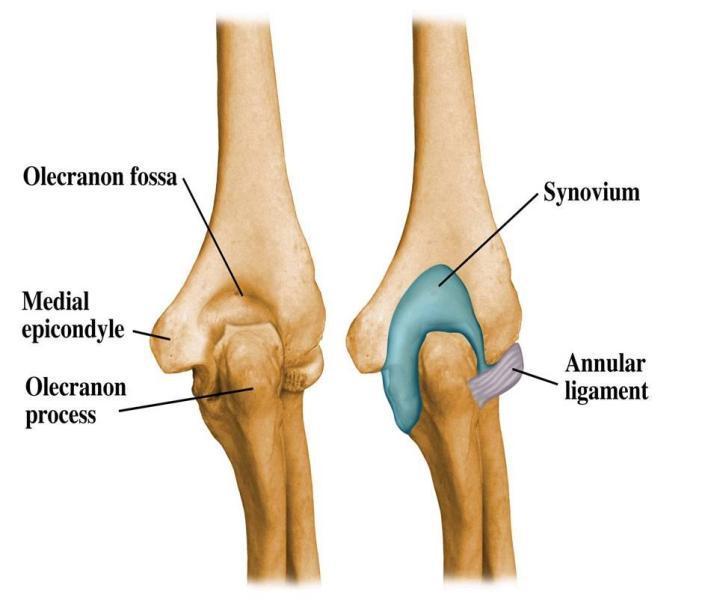

Describe the articulating surfaces of the elbow

Which other joint is also found within the joint capsule of the elbow?

Proximal radioulnar joint

Discuss the stability of elbow joint

Describe the anatomical position of the collateral ligaments of the elbow joint